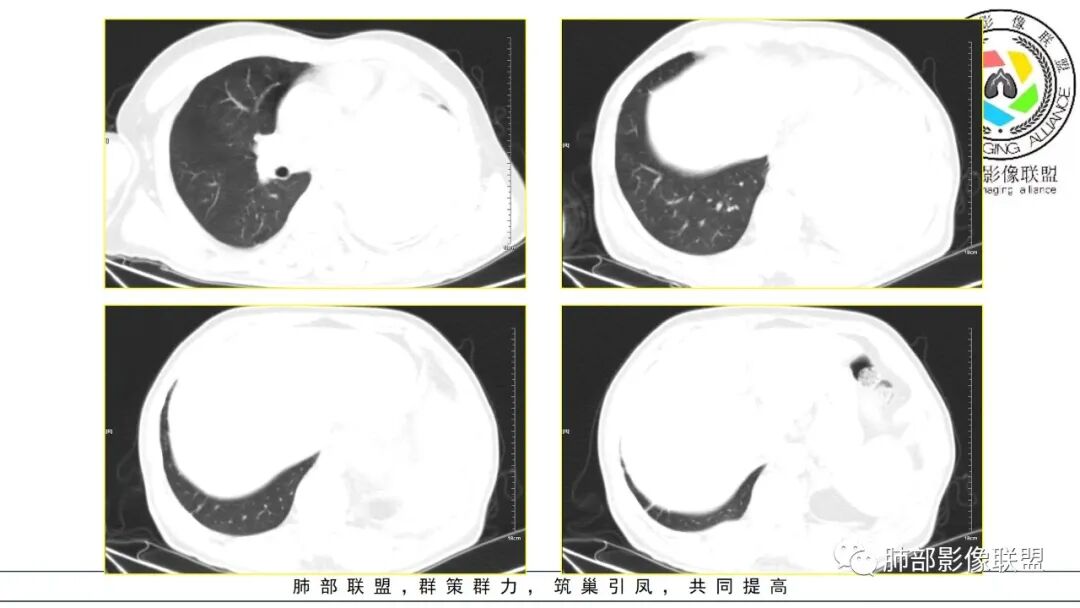

2.左肺巨大块影,上部边界较清楚,占据胸腔大部,对于左肺,“占据”及“推移”兼而有之,左肺上叶支气管推移狭窄,下叶支气管截断。下肺动脉穿行!

3.病灶密度不均,轻度强化,坏死或液化范围甚大,边界可分辨,部分“壁”可见钙化。

4.病灶紧贴胸壁,胸壁未见栽赃侵入。

5.纵隔左移,左肺门变形。左肺门及纵隔未见明显增大淋巴结。